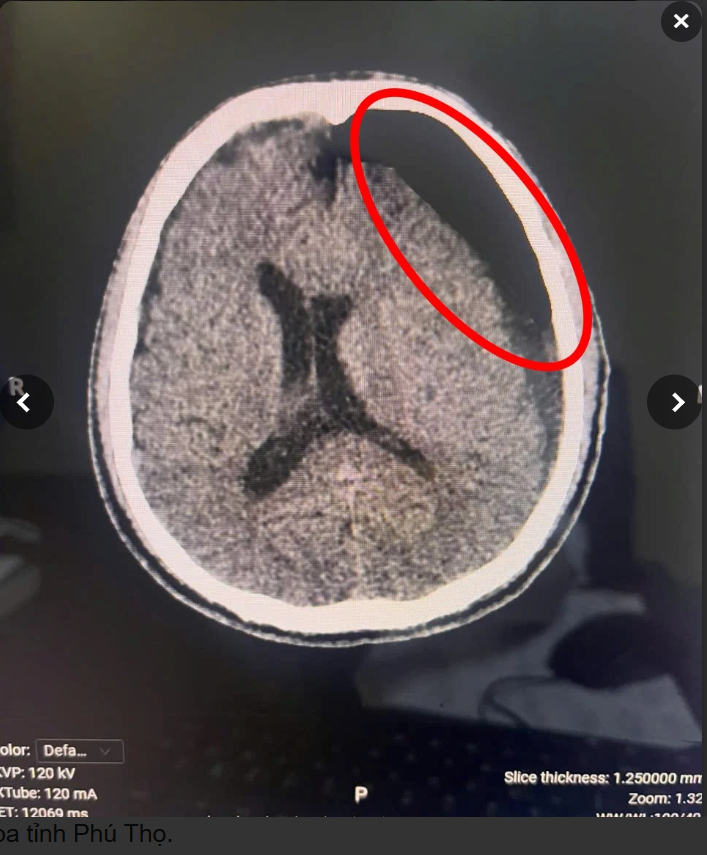

Hình ảnh phim chụp CT sọ não: có khối tụ máu dưới màng cứng giai đoạn bán cấp vị trí bán cầu não trái. Ảnh BVCC

Người bệnh nhập viện tại khoa Cấp cứu trong tình trạng hôn mê, Glasgow 10 điểm. Kết quả chụp CT sọ não cho thấy có khối tụ máu dưới màng cứng giai đoạn bán cấp vị trí bán cầu não trái.